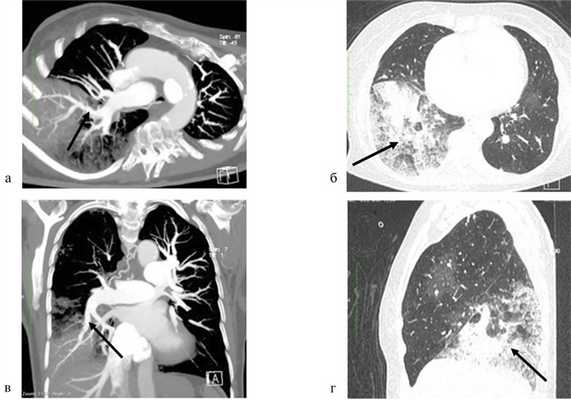

Через 12 ч после завершения операции отмечено ухудшение состояния пациентки: одышка в покое, дискомфорт в правой половине грудной клетки, кашель, снижение сатурации артериальной крови: SpO2 — 86%, PaO2 — 56 мм рт.ст. На контрольной МСКТ органов грудной клетки — картина реперфузионного отека нижней доли правого легкого IV степени (рис. 3). Риc. 3. Мультиспиральная компьютерная томограмма с контрастным усилением через 12 ч после выполнения БАПЛА. а, в — восстановление кровотока в сегментарных ветвях А8, А9 (аксиальный и сагиттальный срезы), стрелками обозначена целевая артерия; б, г — зона реперфузионного отека нижней доли правого легкого в «легочном окне» МСКТ (аксиальный и сагиттальный срезы), стрелками обозначена зона реперфузионного отека.